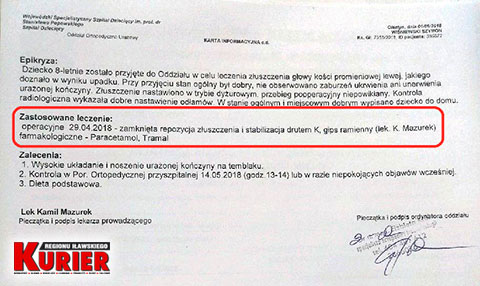

Tego samego dnia matka z dzieckiem zgłosiła się do wojewódzkiego szpitala dziecięcego.

– Pytałam tam doktora, czy na zdjęciu z prześwietlenia w Iławie widać złamanie – mówiła w rozmowie z nami kobieta. – Oczywiście potwierdził i pokazał mi nawet, gdzie dokładnie do niego doszło. Konieczna była prawie godzinna operacja, podczas której ustabilizowano rękę drutem. Przeprowadzono ją od razu, bo lekarz mówił, że każda minuta w tym stanie jest na niekorzyść dziecka.

W olsztyńskim szpitalu podczas operacji

ustabilizowano rękę chłopca drutem